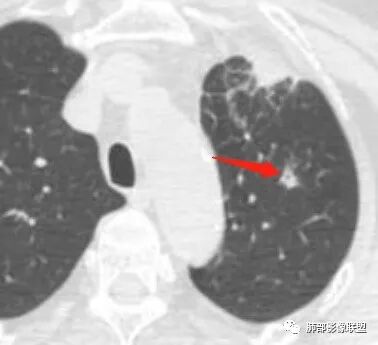

水晶石头: 患者老年女性,咳嗽咳痰10天,痰中带血4天余。查血常规白细胞低;肿瘤标志物、凝血功能正常;血生化:蛋白低;C反应蛋白、血沉稍升高。胸部CT:左肺上叶前段胸膜下沿气管支气管走形肿块影,长轴与胸膜平行,见分叶、毛刺、支气管截断、空泡征象。增强明显强化,且见血管造影征及病灶内小灶低密度坏死区。左肺上叶尖后段见一结节灶。综合考虑恶性病变可能大,腺癌或淋巴瘤可能。鉴别诊断肺脓肿。

3、这个卫星灶,更进一步定了大方向,炎性。